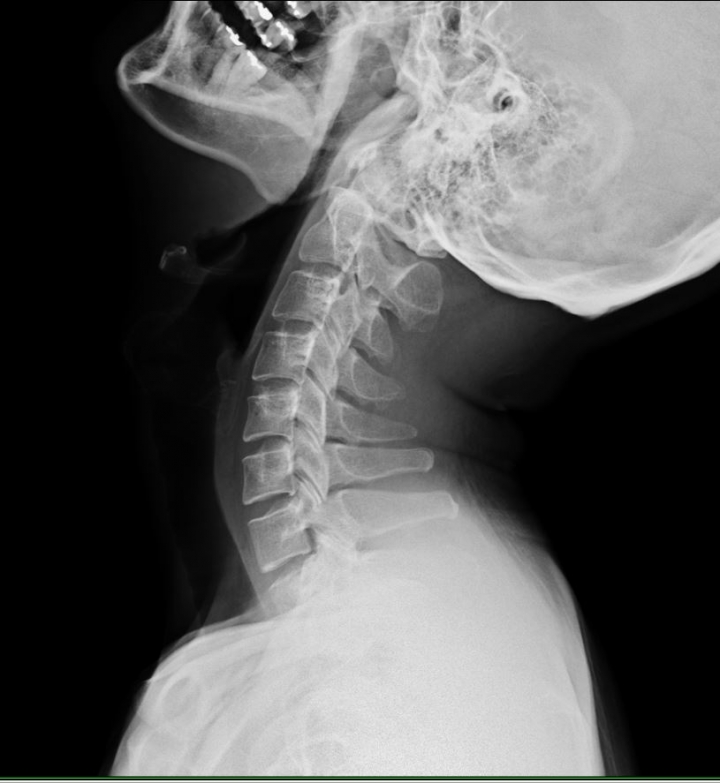

我就去了附近的軍醫院掛了骨科,照了兩張頸椎X光後,醫生說沒事(口氣挺不好),

只說頸椎有點直,叫我回去休息就好...

於是趕緊再去掛了一間骨科(復健科),這次醫生看了X光說,C4、C5、C6有增生!?

而且頸椎變直,叫我要拉脖子復健,就這樣做了半個月的復健,完全沒有好轉,

這次神經外科還是懷疑是頸椎有問題,又幫我照了不同角度的頸椎X光,

醫生看完後說看起來也沒什麼問題,但是我看到X光檢驗師的報告卻寫懷疑C3、C4、C5輕微狹窄?

請問有人看的出來嗎?

這次他認為我的症狀是因為頸椎變直加上之前的睡姿不良導致神經壓迫,